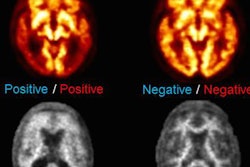

PET scans can track the stages of Alzheimer's disease in cognitively normal adults, according to a new study published in the journal Neuron.

The results of the scans were consistent with the neuropathological stages established by German researchers Heiko and Eva Braak through postmortem analysis of the brains of suspected Alzheimer's patients. These stages range from 1 to 6 and describe the degree of tau protein accumulation in the brain.